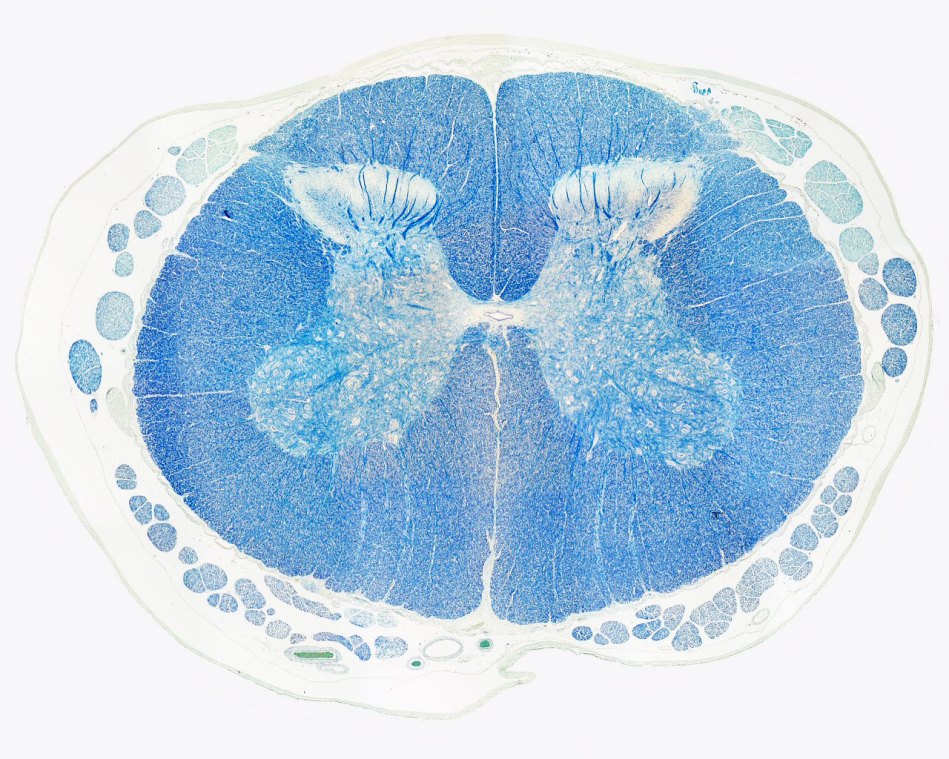

Published February 12, 2020 at 1280 × 1024 in Know your spinal cord – Anterior spinal artery syndrome